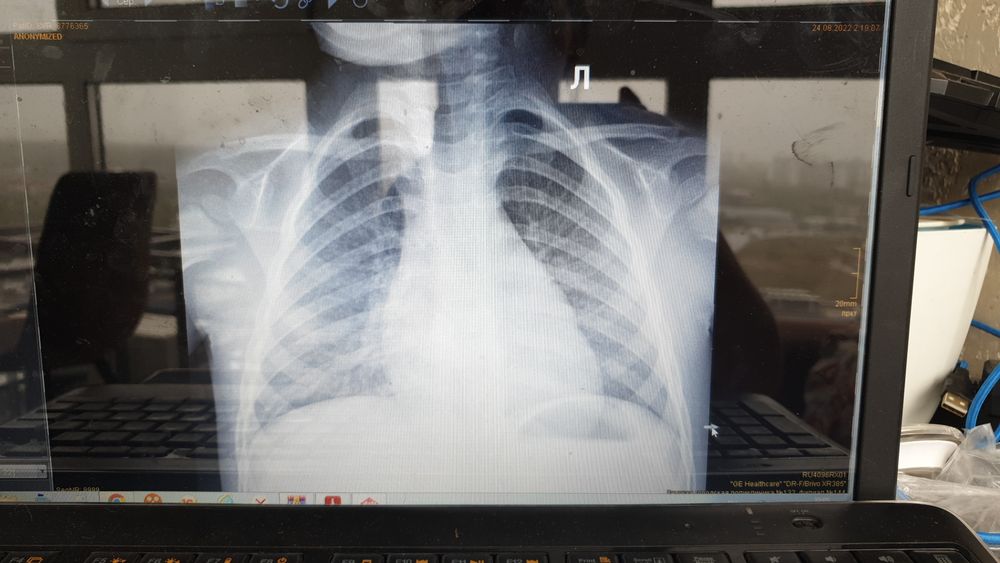

Нужна помощь, ребенку скоро 3 года, кашляет 4 месяц. Сначала думали, что аллергия, но потому сделали снимки, к варчу только в понедельник, может кто знает, что на снимки изображено? Что за болезнь?